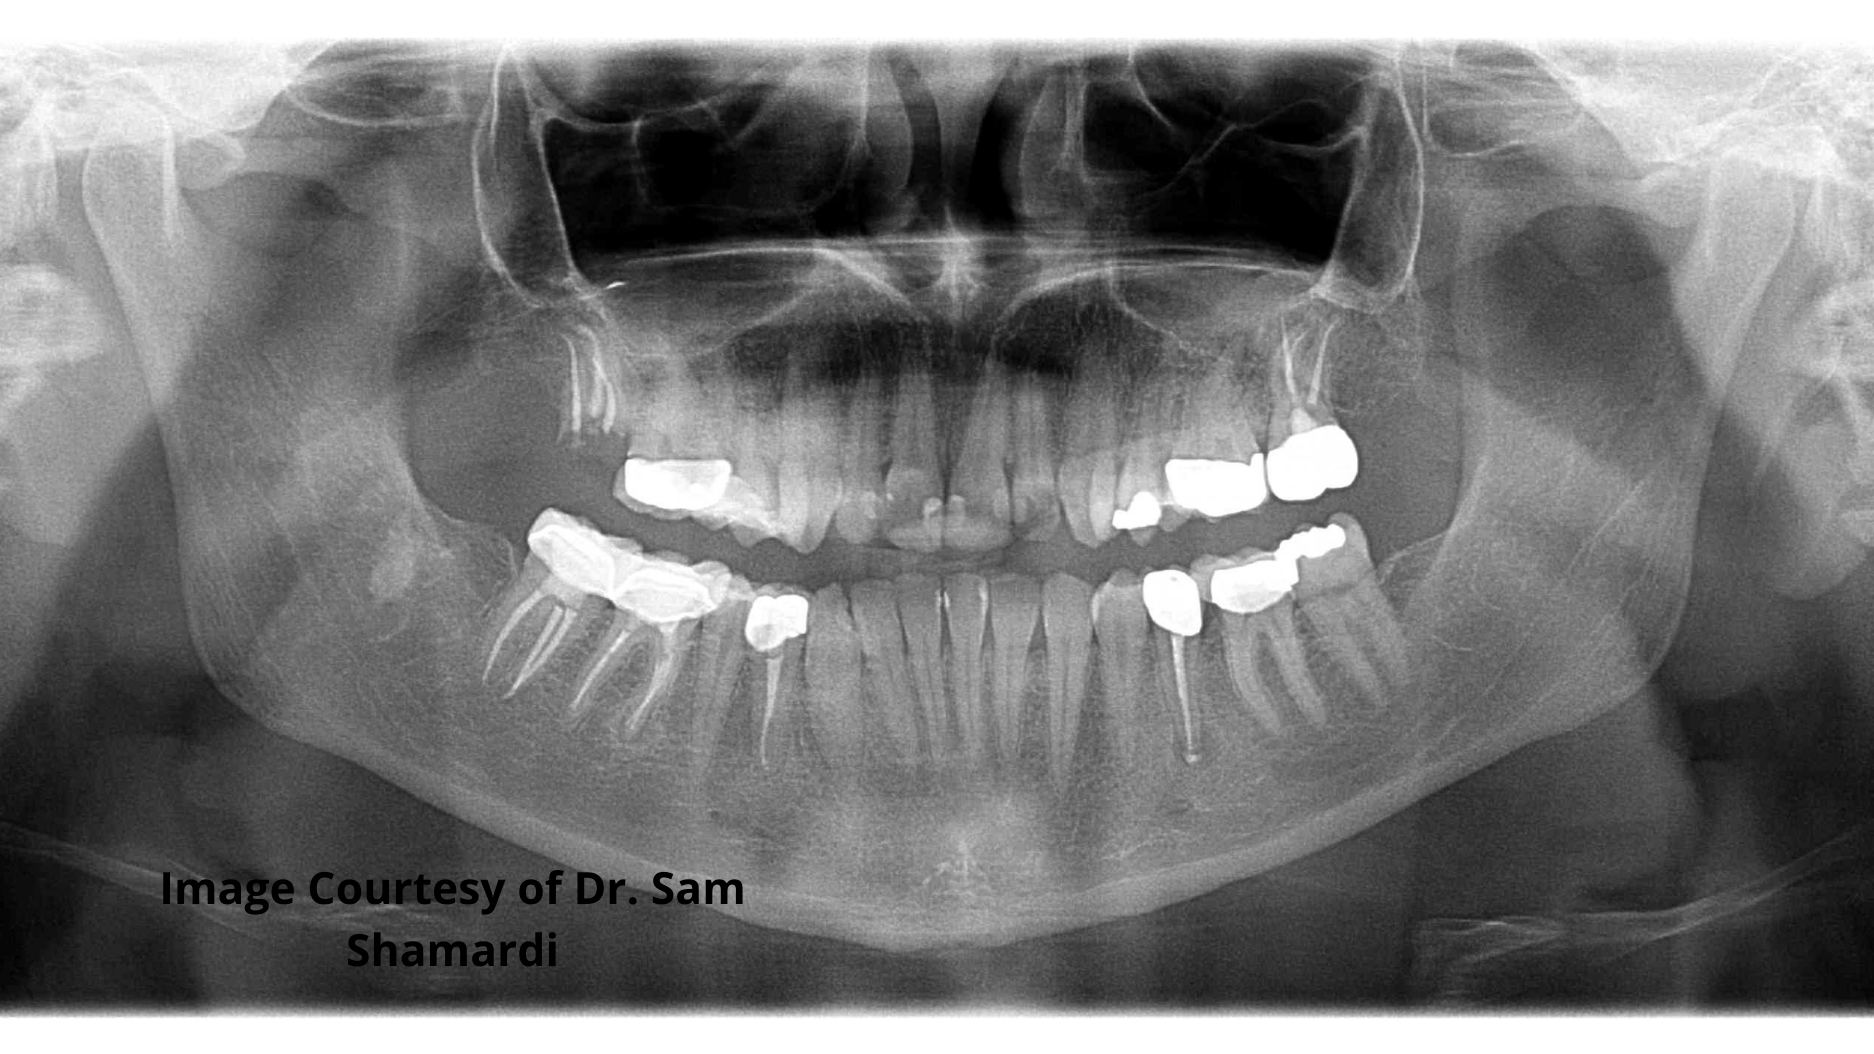

Patient procedure completed: Extraction of residual root tips from fracture of tooth no. 2 and crown lengthening for no. 3.